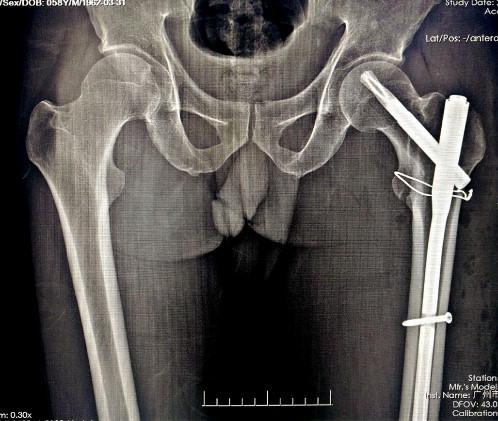

难复性股骨转子间骨折术前

术后

我们复位的技巧是在髋关节前方增加一个五公分左右的DAA切口,用以辅助复位和方便穿过钢丝,复位前尽量外旋股骨远端以帮助解锁,可以用宽骨剥插入骨折断端将骨折近端翘起,此时牵引并内旋、内收股骨远端,残余移位可以通过一条钢丝,利用过钢丝器将钢丝从髂腰肌与股骨矩之间绕过股骨捆扎复位。